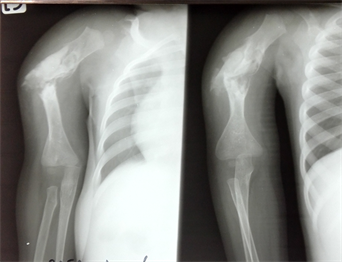

The transplant was introduced into the medullary canal of the Proximal and distal segment of the right humerus (Figure 3).

Stabilization was performed by elastic nail, using retrograde approach, on the lateral epicondyle, without fluoroscopic views. A supplement of 20 ml of granulated bone substitute was required (Figure 4). Additional immobilization by thoraco-brachial plaster was necessary.

Bone consolidation was achieved with a fistula orifice 6 months later. However, bone substitute integration is underway (Figure 4). The clinical results were satisfactory with good mobility of elbow and shoulder (Figure 5).

Figure 4. (a) Massive supplemental bone substitute after stabilization; (b) Postoperative result; (c) Radiographs taken 6 months after elastic nail removal.